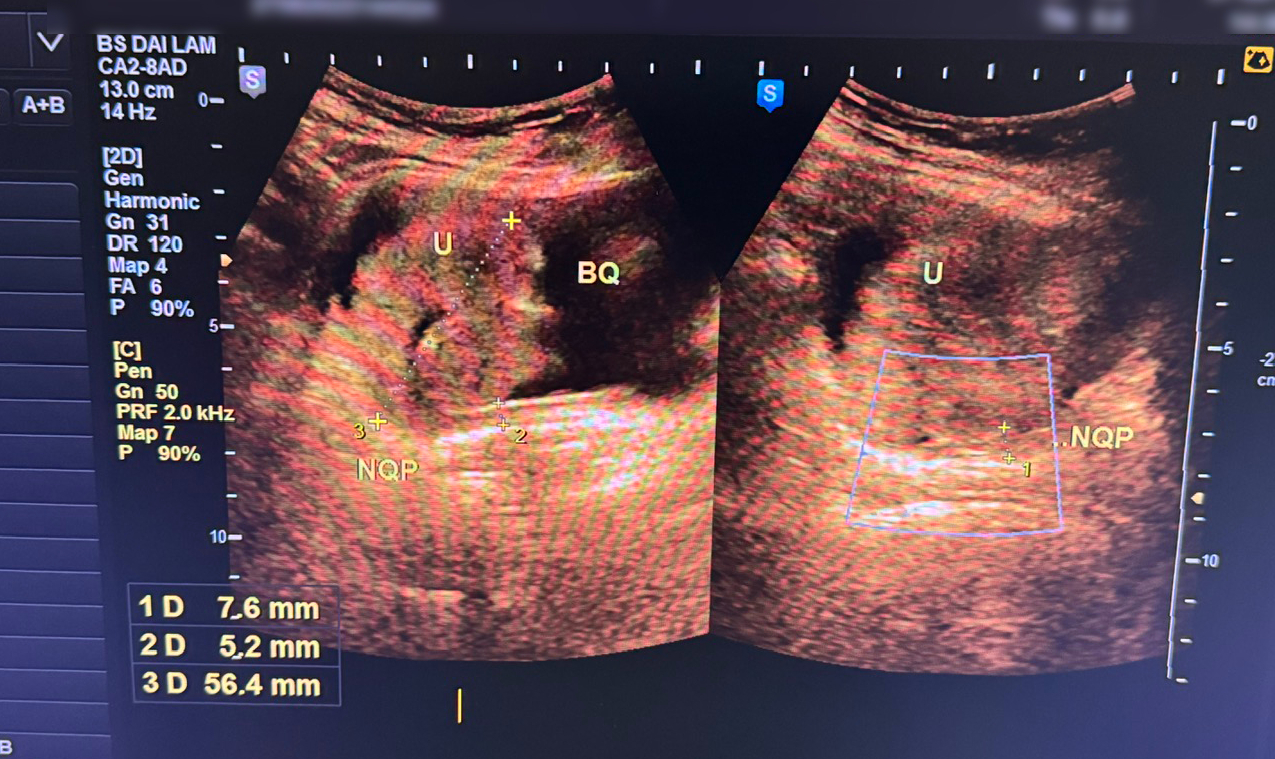

Tại đây, qua thăm khám lâm sàng và thực hiện các cận lâm sàng cần thiết, hình ảnh siêu âm cho thấy thành bàng quang dày không đều, tại đáy bên phải (tam giác bàng quang) xuất hiện một khối tổ chức đặc có xơ hóa, vôi hóa, kích thước 53x54x50mm (khoảng 76 gram). Khối này sùi vào lòng bàng quang, bờ không đều, ranh giới rõ, đồng thời xâm lấn vào niệu quản bên phải gây giãn đài bể thận.

Trên cửa sổ Doppler, khối u có hình ảnh tăng sinh mạch, nước tiểu quan sát không đồng nhất. Với các kết quả thu được, bác sĩ thống nhất chẩn đoán: u bàng quang xâm lấn niệu quản phải. Sau khi giải thích rõ tình trạng bệnh, người bệnh cùng gia đình đã được tư vấn và hướng dẫn lên tuyến trên để tiếp tục điều trị.